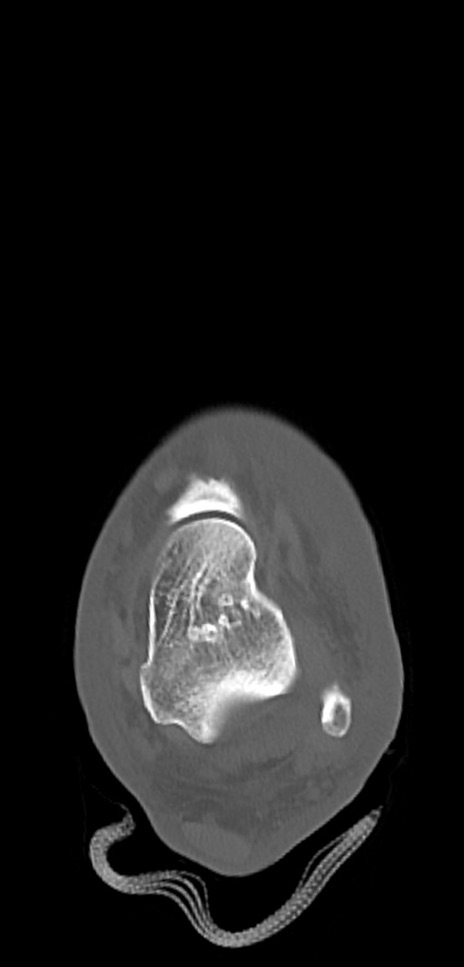

症例37 左足関節CT(横断像)

左足関節CT